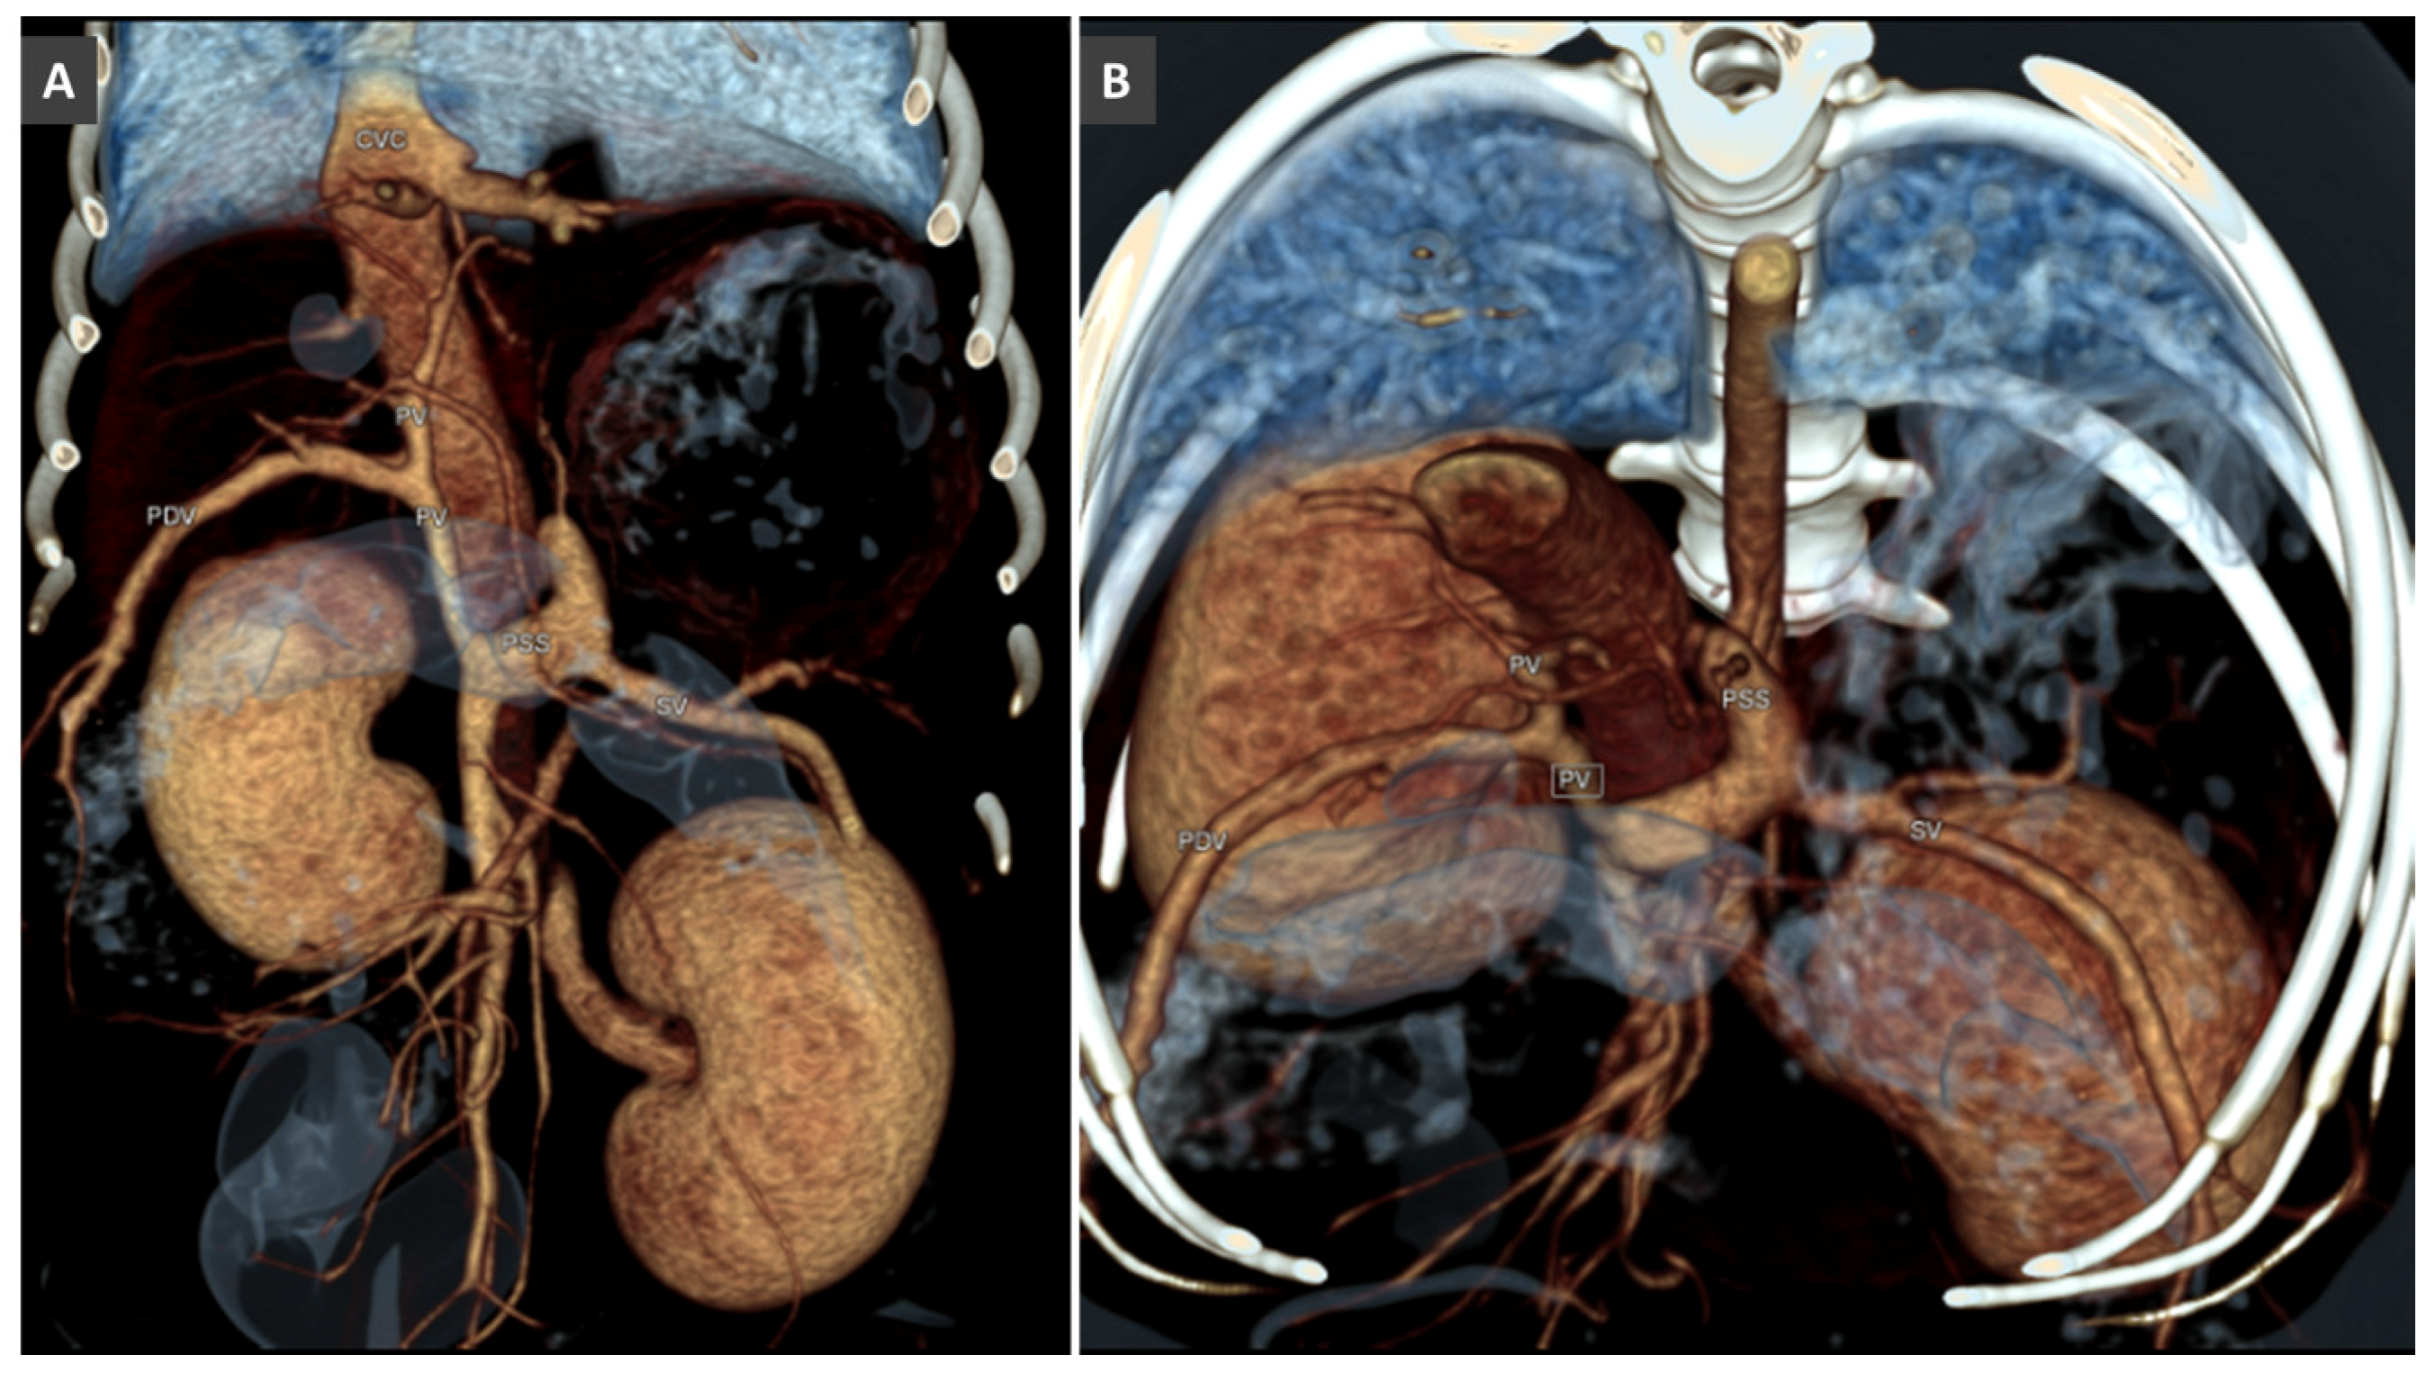

Congenital Portosystemic Shunt

3.8. Porto-Portal Collaterals or Cavernous Transformation of the Portal Vein